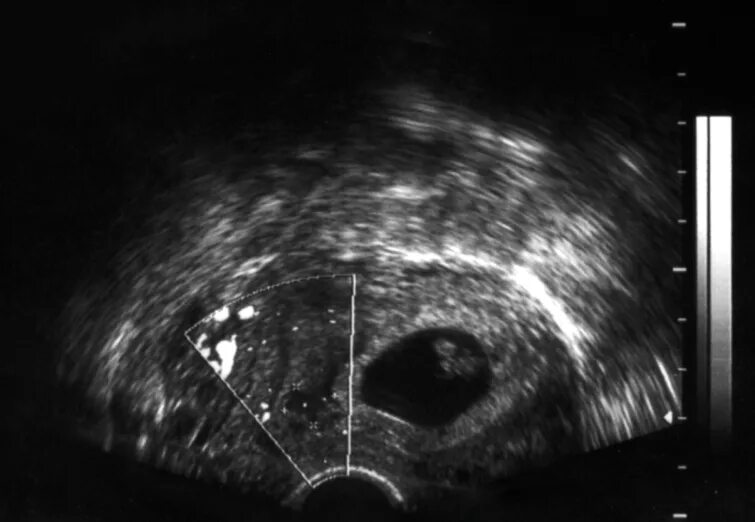

Плод 2 3 недели